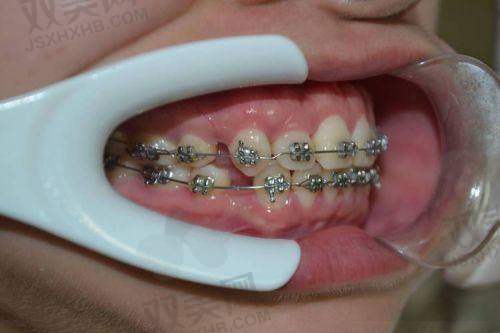

北京禾禾口腔门诊部擅长的项目是口腔正畸!在口腔正畸方面,门诊部可以为患者提供传统金属托槽矫正、陶瓷托槽矫正、隐形矫正等多种矫正方式,满足不同患者的需求。